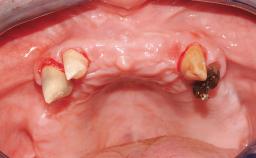

A healthy 31-year-old female patient presented with a failing maxillary left lateral incisor crown. The crown regularly loosened, and the remaining tooth was neither restorable nor rational to treat. The patient had a high smile line, a medium soft tissue biotype with a compromised mesial papilla (shorter than the contralateral one), and a horizontal scar in the buccal soft tissue as a result of past periapical surgery.

| Papilla | Deficient |

| Soft tissue anatomy | Soft-tissue defects |